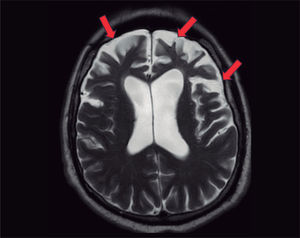

En la resonancia magnética, se visualiza una atrofia de las sustancias gris y blanca frontotemporal.